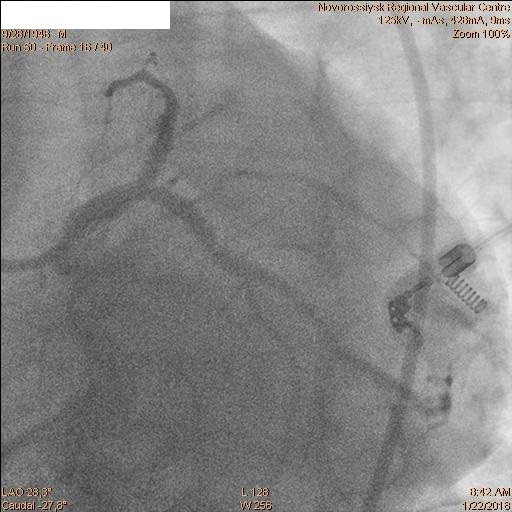

Затем последовательно перепроведены коронарные проводники в дистальные сегмента ПНА и ОА. Баллоном 2.5х20 мм выполнена предилатация ячеек стента. Далее выполнено стентирование ствола ЛКА с переходом на проксимальный сегмент ОА стентом 4.0х28 мм. Затем баллонами 2.5х20 мм и 2.5х15 мм выполнена «kissing» дилатация ствола ЛКА, устья ПНА и устья ОА с великолепным ангиографическим результатом.

Пациент переведен в ПИТ отделения неотложной кардиологии. ЭКГ после операции.